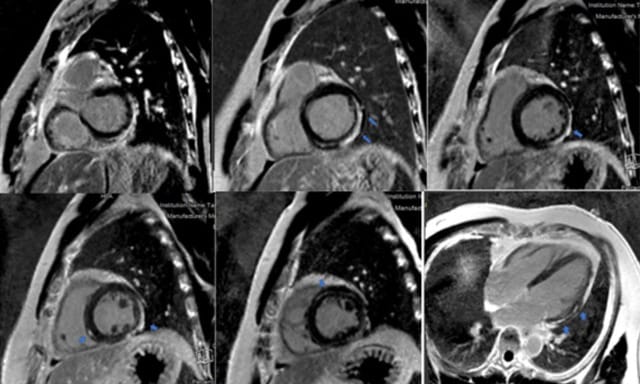

Chụp cộng hưởng từ tim (MRI) giúp phát hiện vùng viêm, phù hoặc hoại tử cơ tim — phương pháp không xâm lấn nhưng rất giá trị trong đánh giá mức độ tổn thương.